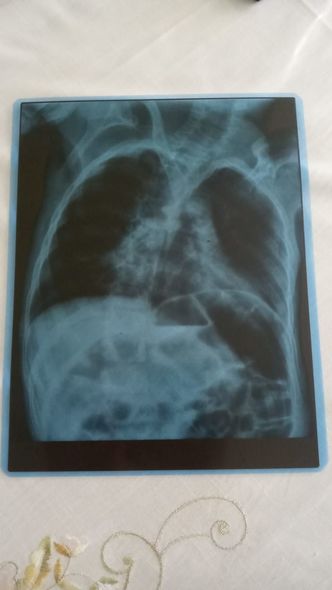

Nərminə Əzizova bildirib ki, Ömərə həm də pnevmoniya diaqnozu qoyulub.

“Öməri soyuq havalarda qətiyyən çölə çıxarmırıq. Qış ərzində ancaq evdə olur. Evin istisinə o qədər öyrəşir ki, çox az müddətə çölə çıxanda xəstələnir. Həkim Ömərə pnevmoniya diaqnozu qoyub. Ömər pnevmoniyaya görə dəfələrlə müalicə alsa da, böyük irəliləyiş olmayıb. Yardımsevər şəxslərin dəstəyi ilə onu həyatda saxlaya bilirik, müalicələrini edirik. Hazırda müalicələrin yarıda qalmaması üçün 150 manata ehtiyacımız var. Ömərin vəziyyəti ilə bağlı mən işləyə bilmirəm, ailəmizdə tək işləyən yoldaşımdır. Ömərdən başqa iki oğlum da var. İnanın, vəziyyətimiz çox ağırdır. Yardımsevər şəxslərdən mənim balama dəstək olmağı, onu bu yolda tək qoymamağı xahiş edirəm”.